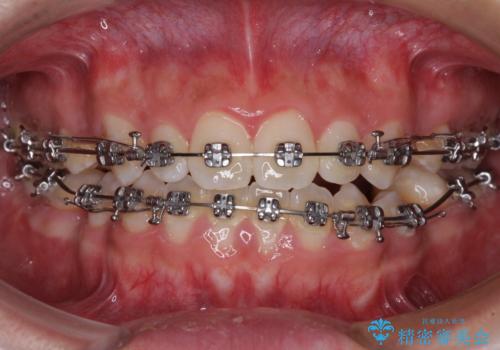

- メタルブラケット

受け口傾向特有の狭い上顎歯列であったため、歯列の拡大を補助装置で行い、下顎歯列全体を後方に移動させることとしました。

奥歯の咬み合わせを改善させた後、上下左右の小臼歯(下顎は残存乳歯)を計4本抜歯し、ワイヤー装置にて口元の突出感を改善しながら咬み合わせを整えることとしました。

受け口傾向の方の抜歯矯正は、下顎前歯が舌側に倒れることで歯肉退縮を起こしやすいことが知られていますが、ワイヤーに工夫をすることでリスクを軽減させています。